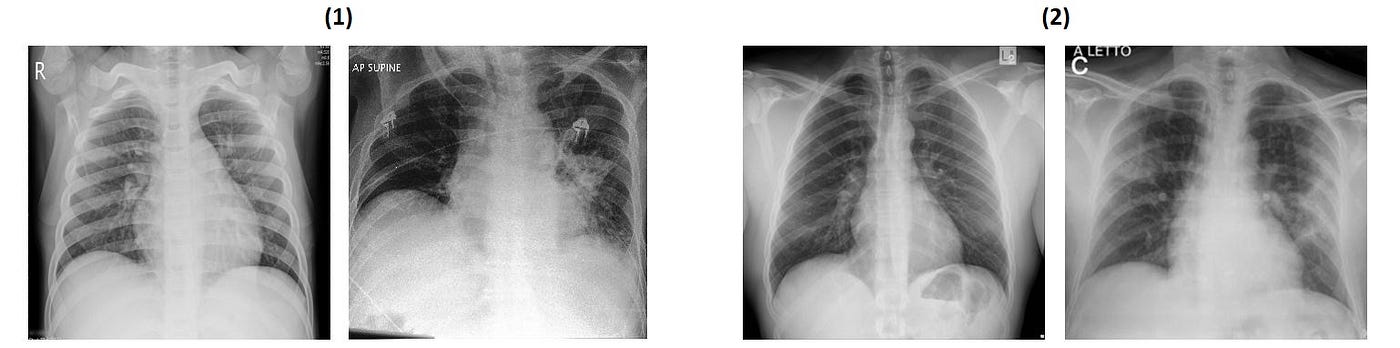

The university of montreal for releasing the images. COVID-19 Chest X-ray Sample | Download Scientific Diagram

It is a simple directory structure branched into test and train and further branched into the respective 3 classes which contains the images. COVID-19 Chest X-ray Sample | Download Scientific Diagram